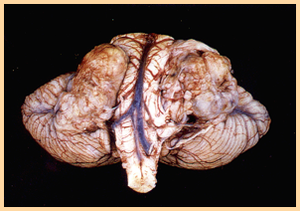

A 95 year old man passes away after experiencing an MI in his sleep. An autopsy of his brain reveals the following changes. His wife states that over the past year he had developed severe memory problems and seemed to have increasing difficulty expressing himself. What is his diagnosis and what types of pathologic changes have occured?

Alzheimer’s disease:

1. Widespread cortical atrophy–> decreased Ach (deficiency of choline acetyltransferase on nucleus basalis of Meynert + hippocampal changes)